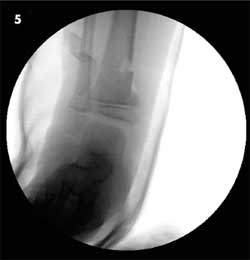

A 6-year-old boy was a passenger on an adult-sized ATV with his uncle. The ATV rolled over on both of them when the uncle lost control. The boy was wearing a chest protector at the time but no helmet. He sustained extensive injuries to both inguinal areas and to his mid-anterior thighs and lower legs. Figure 3 shows an angulated, displaced distal tibia as well as fibula fractures. CT scans and an anteroposterior radiograph of the pelvis (Figure 4) revealed bilateral nondisplaced pelvic bone fractures involving the right superior pubic ramus and bilateral inferior pubic rami. The open right tibia wound was extended surgically, irrigated copiously, and the fracture was reduced. Intravenous antibiotic therapy was administered for 48 hours. A drain was placed in the open wound, and the patient was placed in a long leg cast (Figure 5). The drain was removed in 2 days through an opening in the cast. The patient healed without complications.